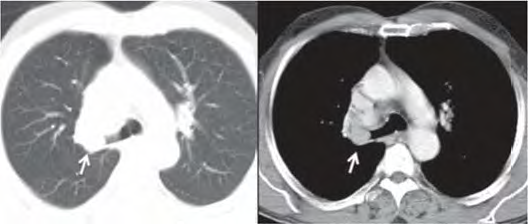

Uma paciente de 47 anos de idade, não tabagista, apresenta episódio de tosse e hemoptise. A tomografia computadorizada de tórax, realizada para investigação, evidenciou um nódulo pulmonar, com densidade de partes moles, de 2,1 cm, com obstrução do brônquio lobar superior direito, demonstrada nas imagens a seguir. Não há linfonodos mediastinais aumentados. A fibrobroncoscopia para investigação evidenciou uma lesão sólida em brônquio lobar superior direito, com obstrução total do brônquio, e aspecto em “dedo de luva”. As tomografias computadorizadas de abdome e de crânio não identificaram lesões metastáticas a distância. A biópsia endobrônquica demonstrou ser um carcinoide típico.

A espirometria permite ressecção pulmonar (lobectomia e pneumonectomia), e a avaliação clínica pré-operatória permite cirurgia de grande porte.

Em relação a esse caso clínico e com base nos conhecimentos médicos correlatos, julgue os itens a seguir.

A paciente tem indicação de lobectomia superior direita com linfadenectomia mediastinal por VATS.